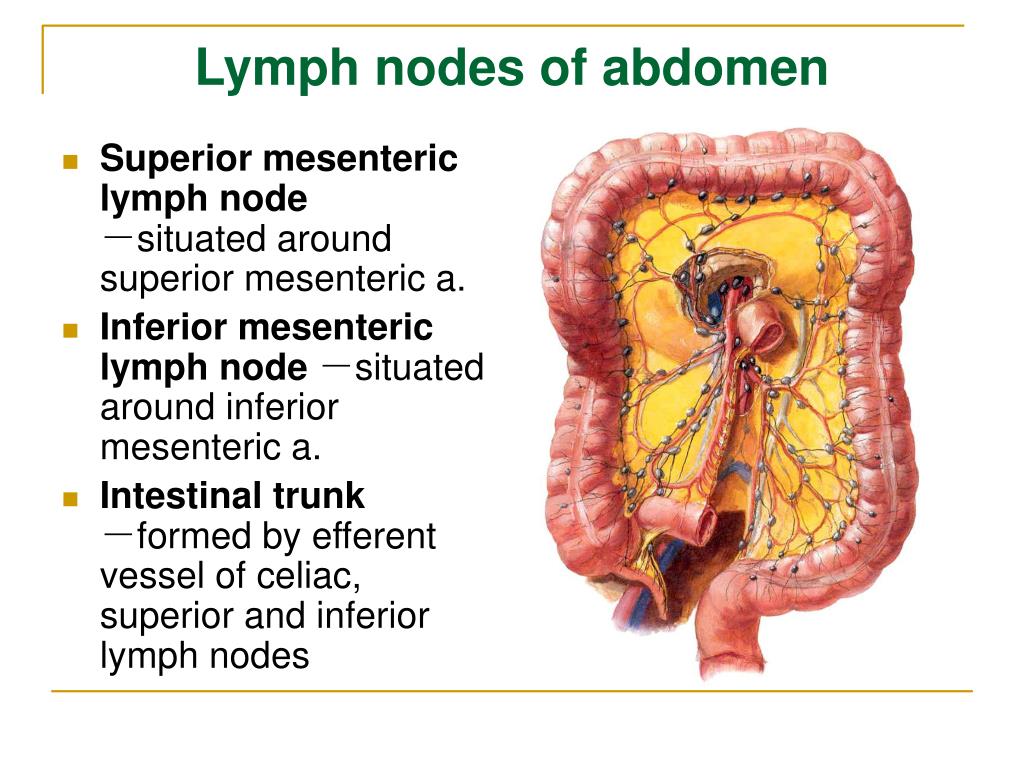

Lymph Nodes Of The Abdomen

guidelistsadampcourse.z14.web.core.windows.net

guidelistsadampcourse.z14.web.core.windows.net

PPT - The Lymphatic System PowerPoint Presentation, Free Download - ID

www.slideserve.com

www.slideserve.com

lymph system lymphatic nodes abdomen presentation ppt node mesenteric superior intestinal powerpoint inferior trunk